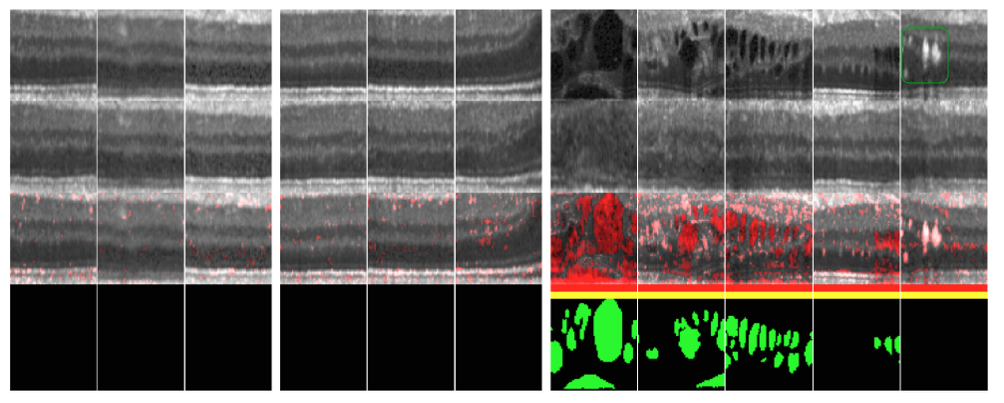

실험 결과를 볼까요? 첫 번째 행은 실제 입력 이미지입니다. 두번째 행은 논문에서 제시한 방법으로 새로 생성한 이미지를 나타냅니다. 실제로 왼쪽 두 블록은 정상 이미지인데 원래 이미지와 새로 생성된 이미지가 매우 유사한 것을 볼 수 있습니다. 반면 가장 오른쪽 블록의 비정상 이미지의 경우 학습된 generator가 원래 이미지를 제대로 복원하지 못합니다. 생성된 이미지와 원래 이미지를 픽셀끼리 비교하면 어떤 부분이 비정상인지를 알려주는 marker를 얻을 수 있게 됩니다.